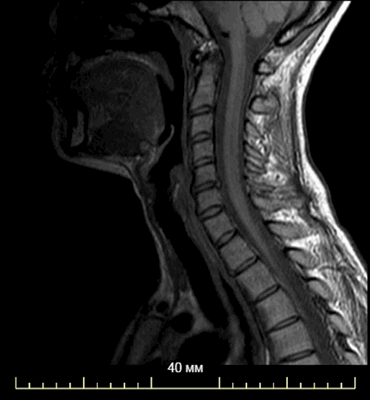

МР-снимок области шеи

Магнитно-резонансное сканирование - безопасный и безболезненный метод. Но процедура имеет некоторые противопоказания. Из-за конструктивных особенностей оборудования МРТ на томографе закрытого типа не выполняют людям с массой тела больше 120 кг. Аппарат не рассчитан на большой вес.

Еще одно ограничение - наличие металлических предметов, имплантированных в тело человека (штифты, стенты и пр.). Если элемент выполнен из титана, последний не исказит сигнал и не повлияет на качество снимка. Нужно сообщить до процедуры об имплантате и предоставить документ с информацией о материале изделия. Противопоказанием к МРТ являются функционирующие устройства: кардиостимуляторы, дефибрилляторы и др.